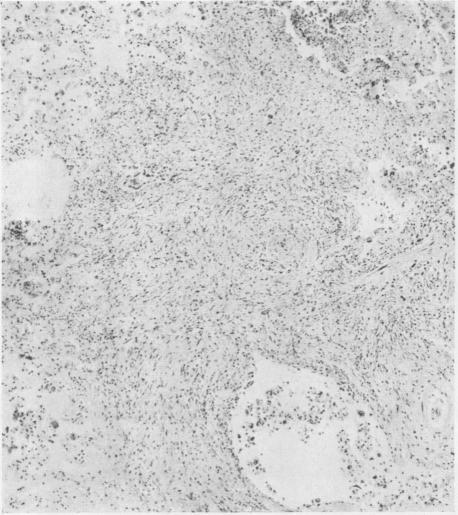

McLAUGHLIN A I G, ROGERS E, DUNHAM K C

Br J Ind Med. 1949 Jul;6(3):184-94. doi: 10.1136/oem.6.3.184.